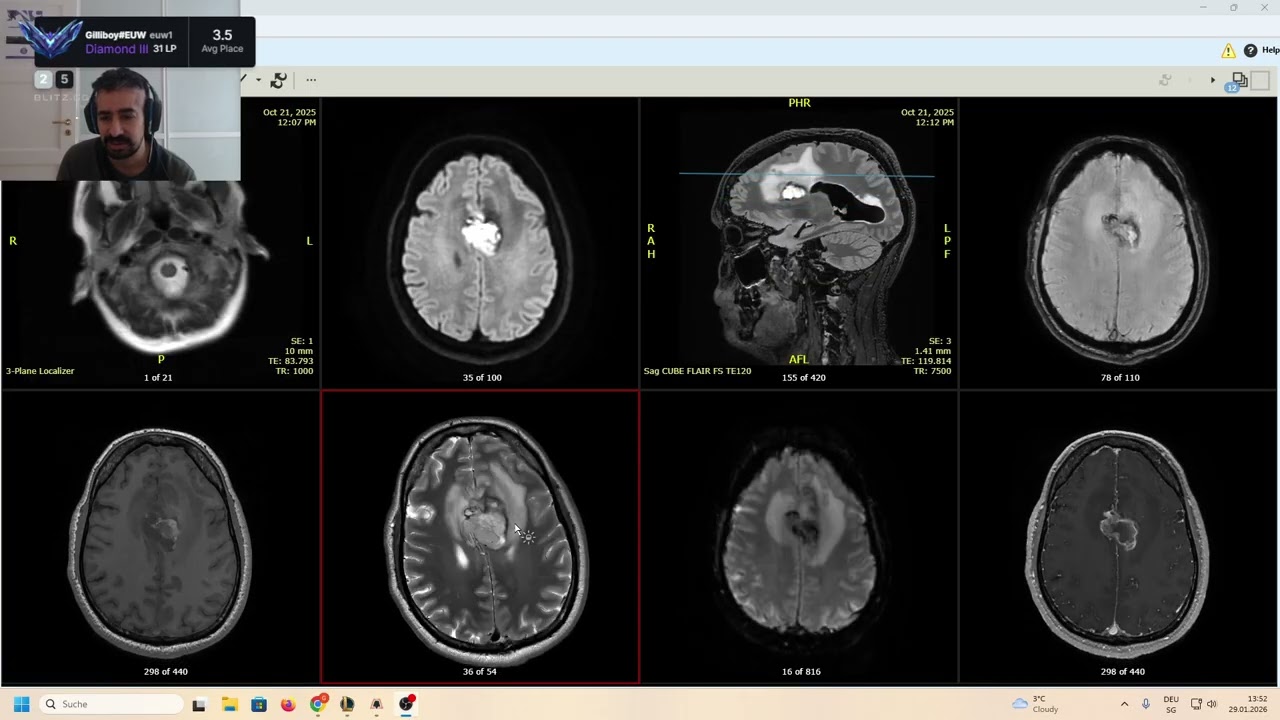

Bienvenue dans Samedi Radiologique #1 avec Dr. Mazouz, radiologue spécialiste en imagerie médicale.

Cette première séance est consacrée à l’imagerie des urgences neurologiques. Découvrez les clés pour analyser rapidement et efficacement un scanner ou une IRM dans les situations critiques, avec des conseils pour interpréter les urgences les plus fréquentes comme les hématomes et les AVC. Une ressource essentielle pour les étudiants et professionnels souhaitant renforcer leur pratique en imagerie neurologique.